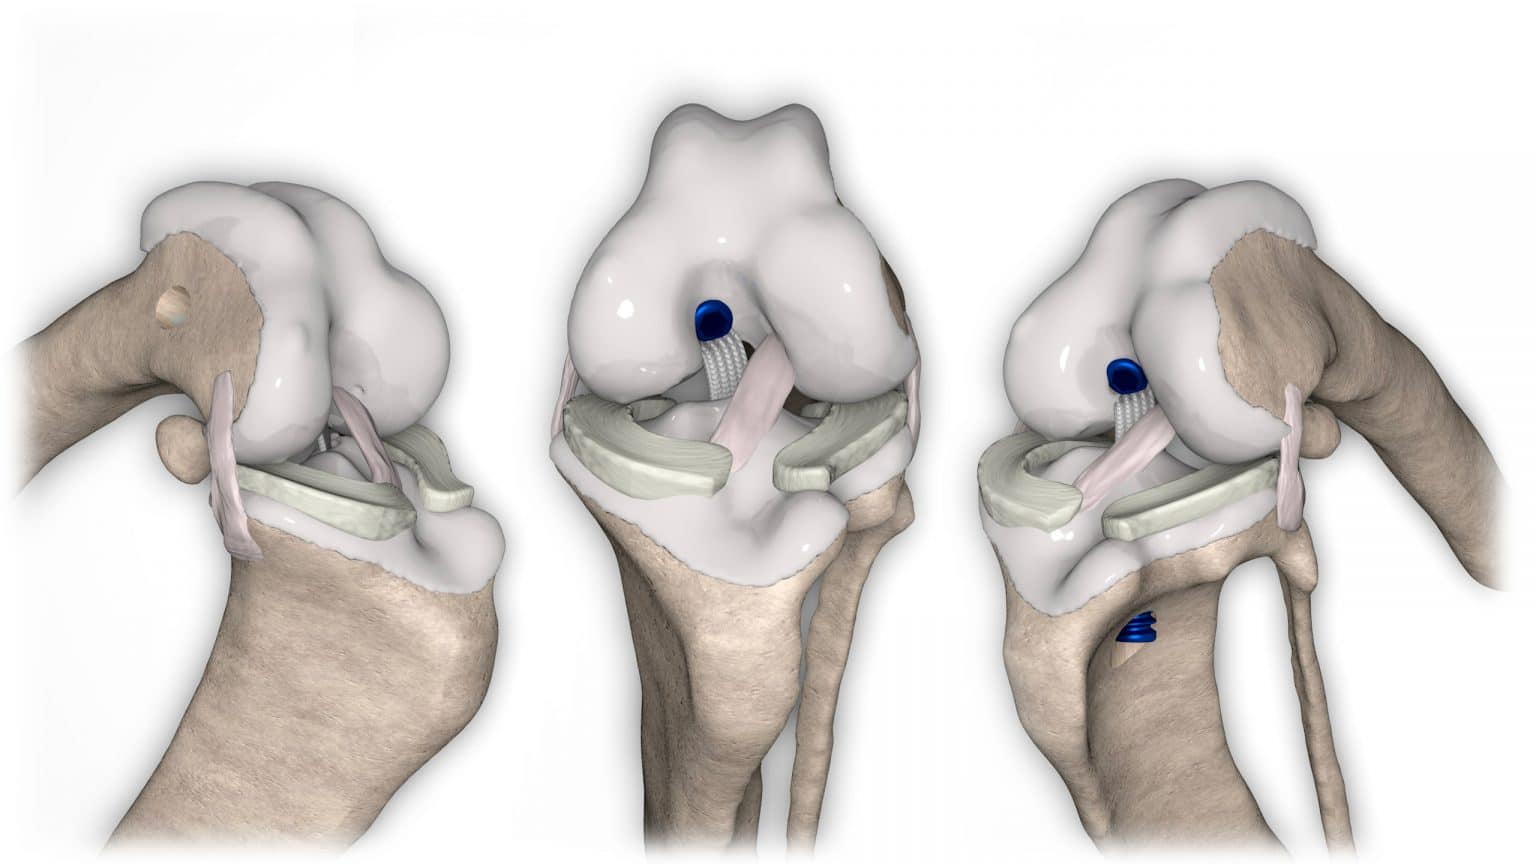

NOVALIG® je syntetický vaz, který lze použít k rekonstrukci vazů a rychlému obnovení jejich fyziologických funkcí.

V případě zkřížených vazů umožňuje intraartikulární rekonstrukci v izometrických bodech připojení, čímž obnovuje biomechaniku kolene a všechny funkce natrženého vazu.

V případě více vazů kolene (kraniální, kaudální, kolaterální) je možné pomocí NOVALIG® anatomicky rekonstruovat každý vaz.